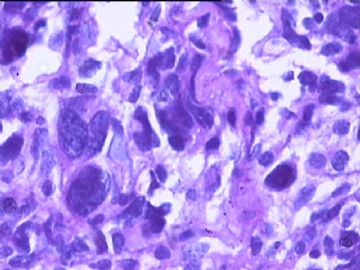

女,34y,头痛一月,右额叶占位:5*5*4cm。囊性区域,4cm。大体:3.5x3x1cm灰白间暗褐色组织一堆,质嫩。临床诊断1:胶质瘤,2:血管母细胞瘤。

同意胶质母细胞瘤。细胞异型、坏死、核分裂、血管内皮肿胀增生均可见到。

This is certainly a WHO grade IV malignant neoplasm. While most likely a glioblastoma, I would carefully rule out PNET by staining for GFAP and neuronal markers such as synaptophysin, NeuN and NSE. Rarely, PNET may shows marked pleomorphism and indistinguishable from glioblastoma on HE stain.

同意马老师的意见,该肿瘤从形态及年龄来看考虑PNET或GBM,须标记Syn、NSE、S-100、NeuN和GFAP来鉴别。

结合图片细胞形态特点考虑胶质母细胞瘤,组化标记排除其他